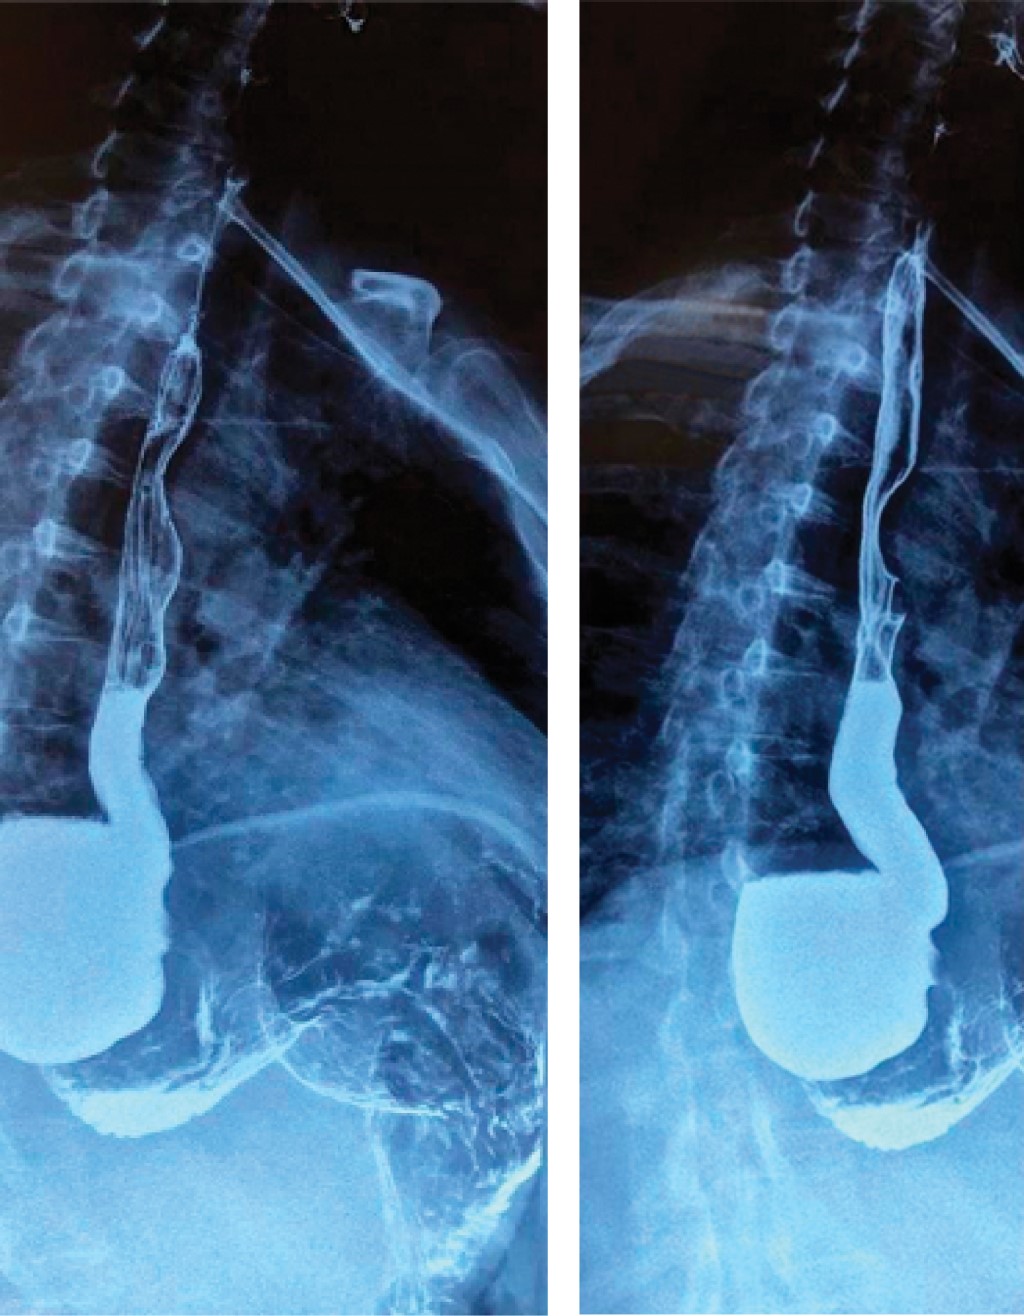

The esophago-gastroduodenal series reported the esophagogastric junction of infra diaphragmatic location, being observed filiform, with a length of 9 mm, and barium passage with a caliber of 14 mm. In addition, a large right posterolateral epiphrenic diverticulum of 5.6 × 7.8 cm with a neck of 2.9 cm was observed (Figure 2).

Figure 2